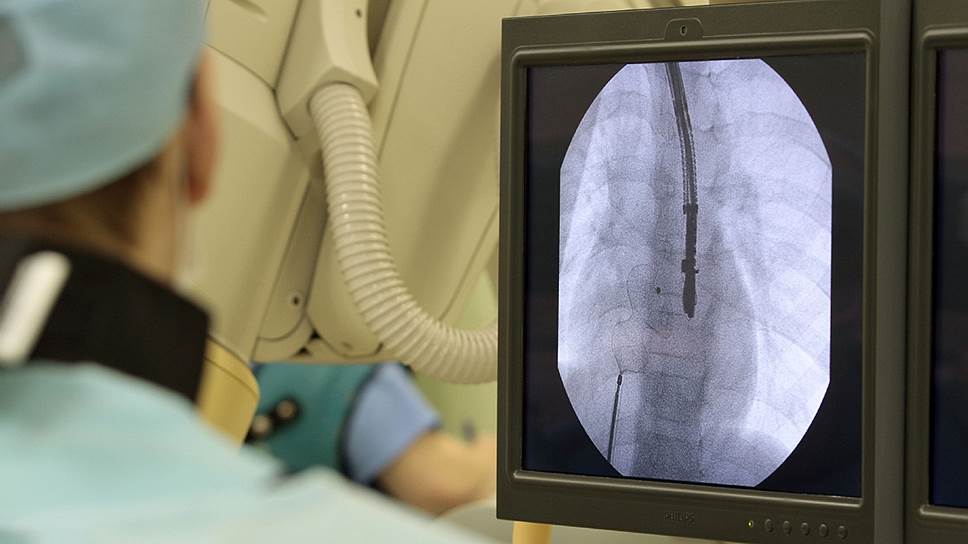

Фото: Интерпресс / PhotoXPress.ru

Один из самых тяжелых врожденных пороков сердца — единственный желудочек; без медицинской помощи прогноз для таких младенцев крайне неблагоприятный. Но современная кардиохирургия позволяет им не просто выжить, но и существовать полноценно. Для этого, в частности, производится операция Фонтена: правое предсердие соединяется с легочной артерией и, таким образом, выполняет функцию правого желудочка, а единственный желудочек работает как левый, обеспечивая кровообращение по большому кругу.

В журнале "Акушерство и гинекология" описан случай благополучного родоразрешения 32-летней пациентки с единственным желудочком сердца, да еще и тромбофилией, то есть повышенной склонностью к образованию тромбов. Группой врачей руководил профессор, доктор медицинских наук Сергей Мравян, ведущий научный сотрудник НИИ акушерства и гинекологии. Роды с помощью кесарева сечения состоялось на 34-й — 35-й неделе беременности, когда обнаружились критические сложности с кровотоком в плаценте; на свет появилась живая девочка ростом 44 см и весом 1990 граммов, синдромом задержки развития плода и небольшой гипотрофией.

Врачам удалось так подготовить пациентку к операции, что ни во время, ни после вмешательства не возникло таких серьезных осложнений, как аритмия или сердечная недостаточность.